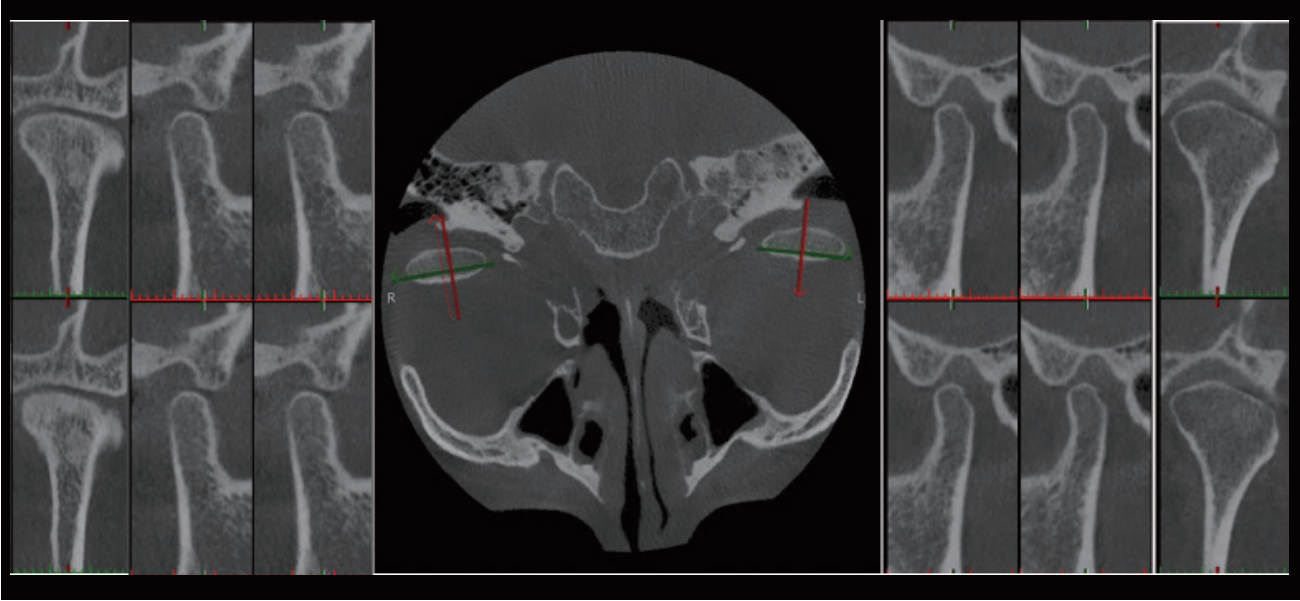

AI + TMJ Analysis

It helps clinicians quickly identify abnormalities such as joint wear, hyperplasia, and sclerosis. By objectively quantifying lesion severity, it reduces missed or incorrect diagnoses, enhances efficiency, and offers valuable reference for orthodontics, implantology, and maxillofacial surgery.

AI+TMJ Automatic Positioning Diagnosis

The display mode of comparing the left and right temporomandibular joints, with the cross positioning line automatically located at the temporomandibular joint, facilitates the diagnosis and treatment of temporomandibular joint diseases by doctors.